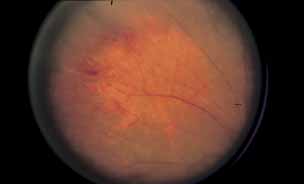

Fig. 16 Eale disease. Color fundus photograph of a 25-year-old Indian man who presented with symptoms of floaters and blurry vision. Note the presence of focal sheathing and hemorrhages along peripheral veins indicative of periphlebitis. The patient later developed neovascular and hemorrhagic complications consistent with Eale disease.